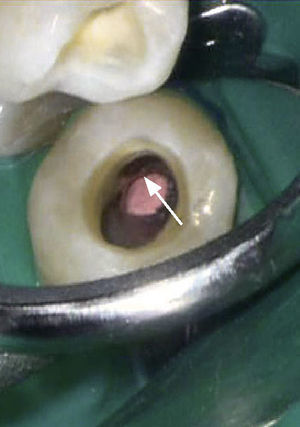

El proceso se inicia a partir de la alteración de la superficie radicular en sentido cervical respecto a la inserción epitelial o a partir de un área que no ha sido recubierta por esmalte o cemento radicular en la germinación del diente13. Posteriormente penetra en la dentina y se extiende hacia apical de forma socavante con una estructura vertical en fase avanzada. La dentina radicular es sustituida por tejido fibroso muy vascularizado y rico en células clásticas. El proceso se desarrolla sin signos evidentes de inflamación. A medida que evoluciona el proceso, se produce una calcificación y un depósito de osteodentina. Hasta el estadio final se conserva una capa fina de dentina y predentina que recubre la cavidad pulpar y aísla al tejido pulpar no inflamatorio del tejido de reabsorción agresivo. Esta capa se observa en la radiografía como una línea radioopaca continua2,4,12,15 (fig. 9).

Se puede observar una tinción de color rojizo de la corona dentaria en las localizaciones muy hacia coronal y el defecto primario se puede sondar (fig. 10). Con frecuencia, los dientes afectados ofrecen un aspecto externo in- tacto, pero muestran una puerta de entrada situada en la zona proximal-cervical. El proceso evoluciona de forma asintomática y el diagnóstico suele ser un hallazgo radiográfico casual (figs. 9 y 11). La prueba de sensibilidad suele ser positiva y la prueba de percusión es negativa. Hay que hacer el diagnóstico diferencial con reabsorciones internas o externas y, en caso de defectos cervicales localizados, con una caries radicular.

Características radiográficasLas reabsorciones cervicales invasivas se caracterizan por los signos radiográficos siguientes:

Origen en el límite amelocementario.

Línea radioopaca alrededor de la luz del conducto (predentina).

Aspecto marmóreo del defecto.

Forma perimetral errática.

Orientación longitudinal.

Espacio periodontal continuo.

Debido a su tamaño, las reabsorciones de clase 3 y 4 requieren un tratamiento endodóntico (fig. 11). Se hallan depósitos de calcificaciones ectópicas sobre la superficie de la dentina y tejido osteofibroso muy vascularizado, los cuales se eliminan con fresas redondas de tallo largo y puntas ultrasónicas7,15. El procedimiento requiere una irrigación continua y varias sesiones de tratamiento con uso de hidróxido de calcio y Ledermix como medicación intraconducto. Se recomienda el uso tópico de ácido tricloroacético para la escarificación del tejido agresivo que infiltra la dentina6. A continuación se obtura la porción apical del conducto bajo el microscopio quirúrgico con gutapercha plastificada y sellador mediante compactación vertical. La laguna de reabsorción propiamente dicha se rellena con MTA. Mediante la transmisión indirecta de ultrasonidos al atacador el material se fluidifica y rellena con precisión toda la luz de la reabsorción15–17 (figs. 12 y 13). Los defectos coronales se pueden tratar directamente en función del grado de destrucción de la sustancia dura mediante la técnica adhesiva con composite o con una restauración prefabricada en el laboratorio (fig. 14).